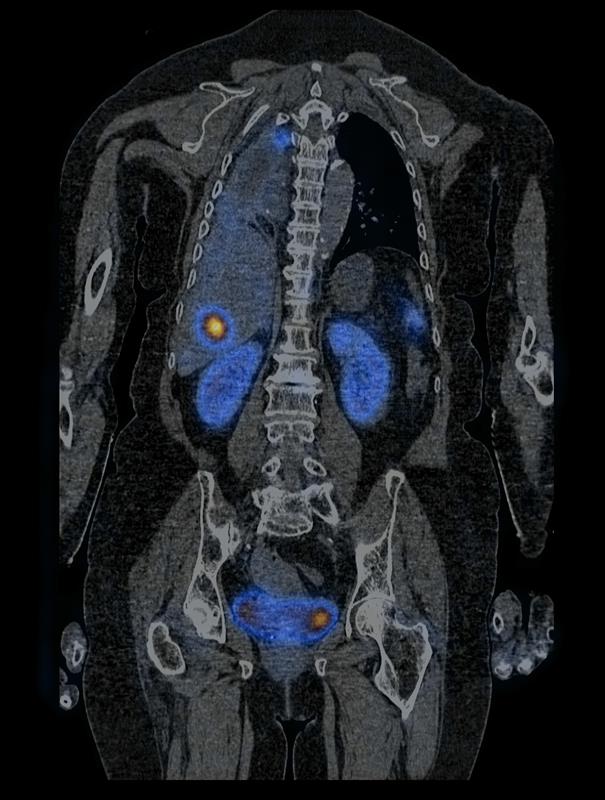

Po raz pierwszy w województwie zachodniopomorskim zastosowano terapię radioizotopową z wykorzystaniem radiofarmaceutyku 177Lu Lutathera u pacjentki z rozpoznaniem atypowego rakowiaka płuc z obecnością przerzutów. Zrobiono to 11 maja w Zakładzie Medycyny Nuklearnej w Samodzielnym Publicznym Szpitalu Klinicznym nr 1 w Szczecinie. To nowoczesna forma leczenia guzów neuroendokrynnych i od kilku miesięcy terapia ta jest objęta refundacją w ramach programu lekowego.

177Lu Lutathera łączy się z receptorami znajdującymi się na powierzchni komórek nowotworowych. Ponadto radiofarmaceutyk ten zawiera radioaktywne izotopy, które emitują promieniowanie jonizujące. Promieniowanie uszkadza DNA komórek nowotworowych, powodując niszczenie lub zahamowanie ich zdolności do podziału i wzrostu. Podobne działanie promieniowania jonizującego stosuje się w radioterapii. Dzięki selektywnemu łączeniu się z komórkami nowoworowymi, radiofarmaceutyki terapeutyczne są w stanie skutecznie zwalczać komórki nowotworowe, a emitowane promieniowanie, z uwagi na bardzo krótki zasięg, nie powoduje znaczącego uszkodzenia zdrowych tkanek.

– W Zakładzie Medycyny Nuklearnej w Szczecinie leczenie 177Lu Lutathera zostało zaprojektowane z myślą o spersonalizowanym podejściu do każdego pacjenta – informuje dr Joanna Woźnicka, rzeczniczka szpitala klinicznego nr 1 w Szczecinie. – Przed i po leczeniu przeprowadza się badania obrazowe, które umożliwiają ocenę tempa metabolizmu znacznika, które różni się u poszczególnych pacjentów. Pozwala to na dostosowanie terapii do indywidualnych potrzeb i zwiększa szansę na osiągnięcie pozytywnych rezultatów terapeutycznych. Ta innowacyjna forma terapii, łącząca działanie molekularne i promieniowanie jonizujące, otwiera nowe perspektywy w zwalczaniu nowotworów. Dzięki ciągłemu rozwojowi nauki i technologii coraz więcej pacjentów może skorzystać ze skutecznych i bezpiecznych metod terapeutycznych, które mają na celu zahamowanie wzrostu komórek nowotworowych i poprawę jakości życia pacjenta.